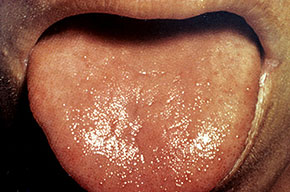

Three basic skin eruptions occur in pellagrins . The first is a photo-induced eruption that is intensely erythematous and subsequently exfoliates to yield a hyperpigmented residuum. The second eruption comprises painful erythematous erosions in genital and perineal areas possibly induced by pressure, heat, and trauma . The increased skin fragility may reflect aberrations in the collagen and elastic fiber content of the skin. Pellagrins may develop a seborrheic dermatitis-like rash involving the face, scalp, and neck. Oral manifestations include beefy, red, cracked lips and a fissured or smooth, red, sore tongue . Among the neurologic symptoms are dementia, psychosis, anxiety, defective memory, burning sensations, sudden attacks of falling, dizziness, and headaches. A cause of sudden death is central pontine myelinolysis .